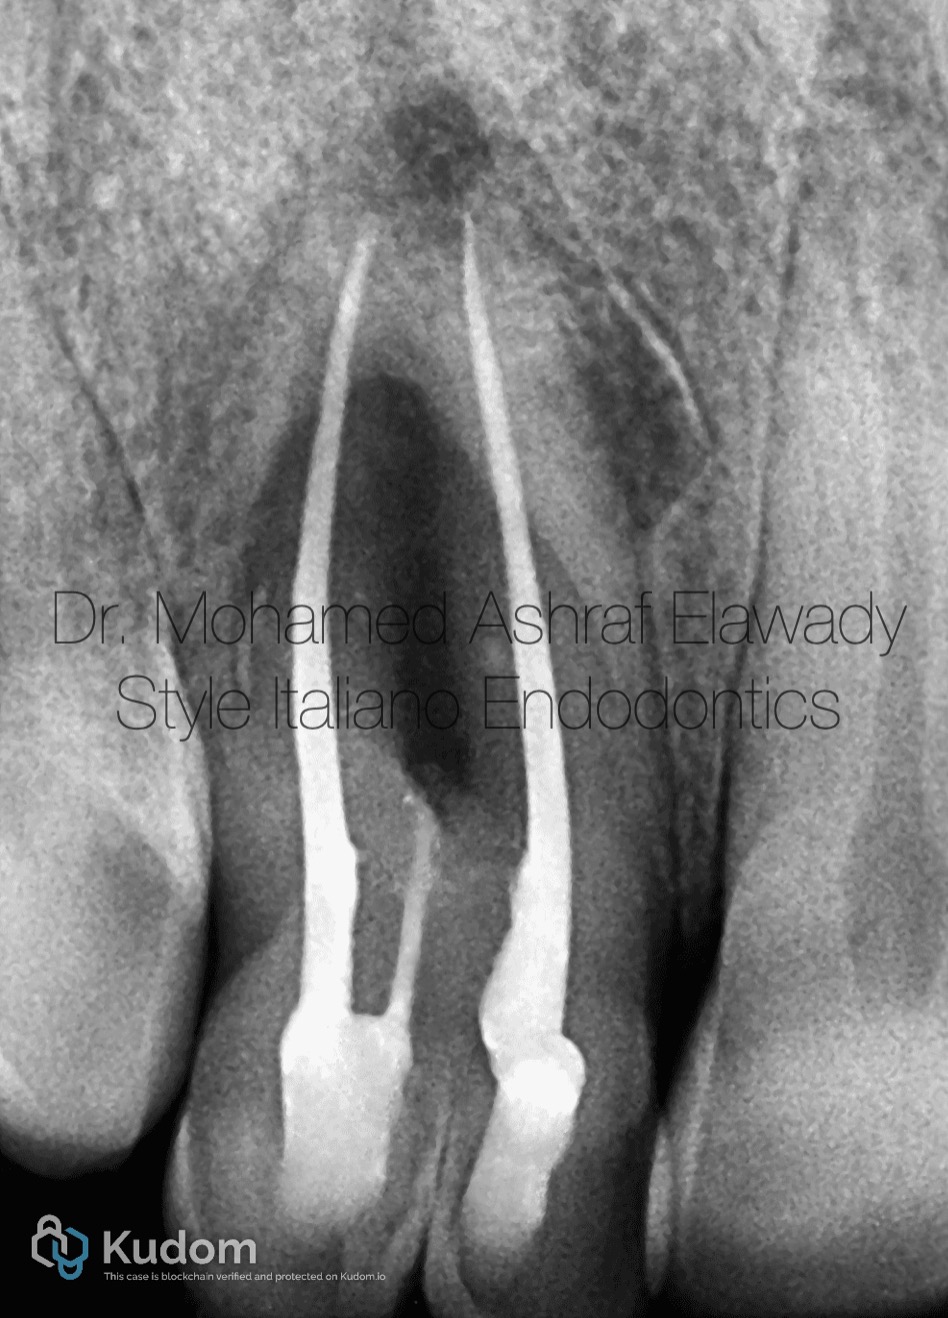

The management of a necrotic maxillary lateral incisor presenting with fusion and Type III dens invaginatus associated with a periapical lesion represents one of the most biologically and technically demanding scenarios in contemporary endodontics. The coexistence of fusion—resulting in enlarged crown morphology and complex, often interconnected canal systems—with Type III dens invaginatus, characterized by a deep enamel-lined invagination extending through the root and communicating with the periodontal ligament, creates a highly irregular internal anatomy. This configuration permits early microbial contamination through the invaginated tract, often leading to pulpal necrosis and extensive periapical pathology independent of the primary canal system . Effective management requires a precise diagnosis supported by three-dimensional imaging, particularly CBCT, to delineate the true canal anatomy, identify separate foramina, and assess the extent of the periapical lesion. Treatment should follow a biologically based protocol focused on maximal disinfection while preserving structural integrity. Careful access under magnification, ultrasonic refinement, and strategic negotiation of both the main canal and invaginated lumen are critical. Enhanced irrigation protocols with activation techniques are essential to address inaccessible recesses. Intracanal medicaments such as calcium hydroxide may aid in microbial control prior to definitive obturation. In cases of persistent pathology, obturation for dens in dente must be done with bioactive biocompatible material to achieve good seal in Periodontal ligament area.

Preoperative Xray

Obturation with ah plus resin sealer and gutta-percha for the 2 main canals and mta for dens in dent as bioactive biocompatible material for Sealing this area, play a vital role in obturation by providing excellent sealing properties, biocompatibility, and resistance to shrinkage. Their hydraulic properties allow them to adapt well to canal irregularities, offering superior resistance to bacterial penetration, promote tissue healing, enhancing long-term outcomes.